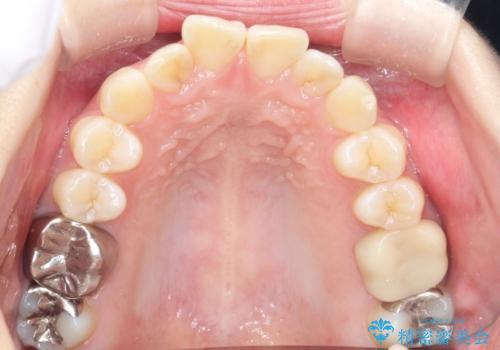

前歯のガタつきをマウスピース矯正で改善

- 前歯のガタツキが気になると来院されました。

奥歯の噛み合わせは綺麗に噛んでいたため、前歯の叢生(でこぼこ)に集中して治療するように計画しました。